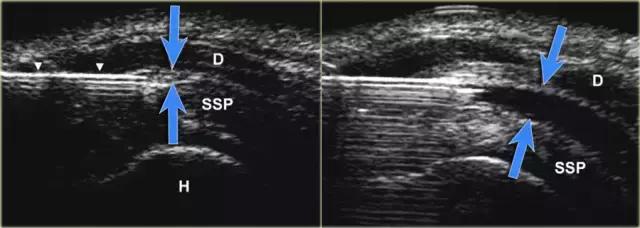

前路途径 在前路方法中,患者仰卧仰卧,伸出的手臂外旋(图)。超声探头在腹侧平行于肩胛腱的长轴放置。探头侧的灰线表示长轴。

使用22号针,针连接到包含造影剂的50mL注射器,由助手保持,在适当的针位置注射15-20mL造影剂时,针垂直于肱骨头的内侧边缘前进,穿透肩胛腱。

如果刺中肱骨头的软骨,针应该拉回1或2毫米,稍微倾斜大约15◦,然后前进切向与头部进入关节,针的斜面朝向关节(图) 。不应该感觉到注射阻力,并且应该看到对比剂自由进入关节并且存在于肩胛下凹部中。